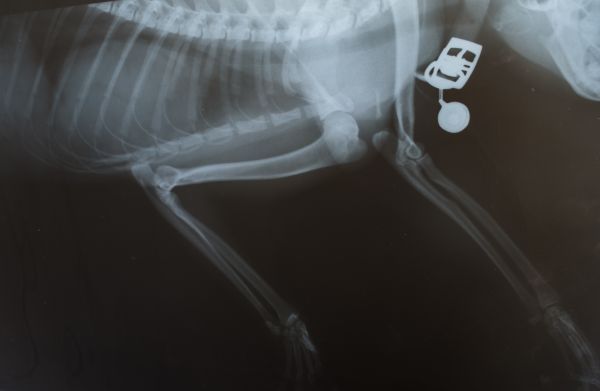

Radiographs

X-rays may reveal the presence of larger than normal amounts of fluid or arthritis in the joint, as well as any bone abnormalities. Radiographs usually require a sedation to allow for positioning of the joint for diagnostic accuracy.

Diagnosing cruciate disease may be presumed by findings on the physical examination, and confirmed with radiographs under sedation, when the cranial drawer test can be repeated.